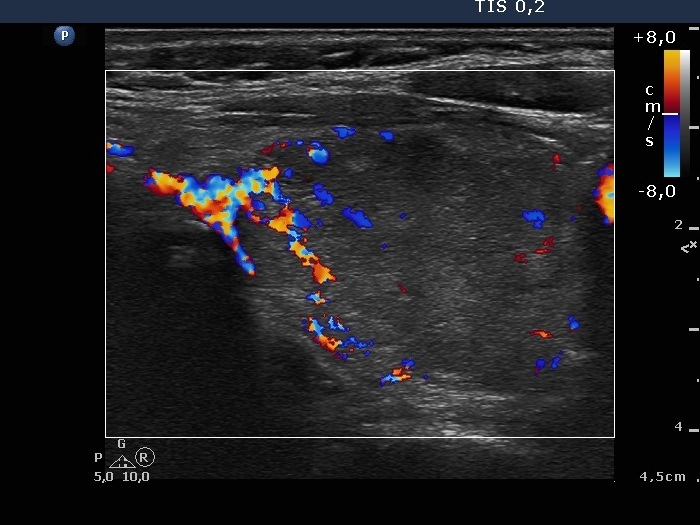

Ultrasonography. The thyroid was echonormal. There was a small, moderately hypoechogenic nodule in the right lobe, while the left lobe contained multiple nodules with different echogenicities.

The moderately hypoechogenic nodule in the lower pole of the right thyroid was aspirated. We gave a combined cytological-ultrasound diagnosis of benign follicular proliferation.